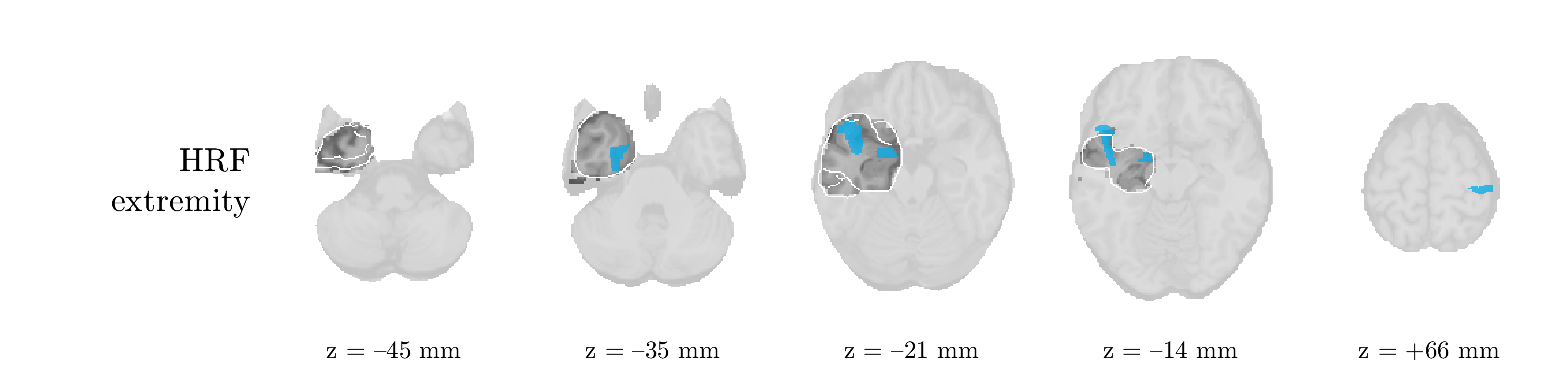

Patient 9

We analyze the solution with sources, and show the results in Figure 15 and 16. In this patient, there is only a moderate correlation of a component with the MWF reference time course. This component’s topography (left occipital) agrees with the clinical description, however. The HRF extremity (and not the entropy) is high in a small part of the IOZ. Both the significant IED activation and deactivation allow correct localization as well. The second source seemingly captured high-frequency oscillatory activity in the sensorimotor network, similar to the previous patient.